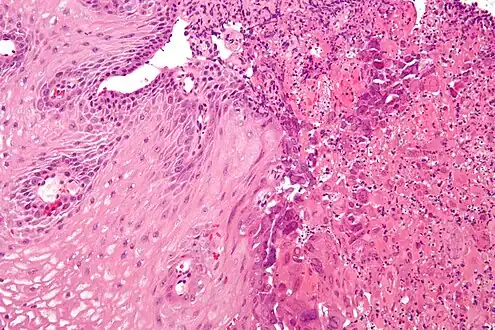

Micrograph of an esophageal biopsy showing herpes eosphagitis, with the characteristic nuclear changes (nuclear moulding, chromatin clumping at the nuclear membrane (margination) and multinucleation). H&E stain.

Upper Endoscopy often reveals ulcers throughout the esophagus with intervening normal-appearing mucosa. In severe cases the ulcers can coalesce and on rare occasions have a black appearance known as black esophagus.[8] While the diagnosis of herpes esophagitis can be inferred clinically it can only be accurately diagnosed through endoscopically obtained biopsies with microscopic evaluation by a pathologist finding the appropriate inclusion bodies and diagnostic immunochemical staining.[9] False negative findings may occur if biopsies are taken from the ulcer rather than from the margin of the ulcer as the inclusion particles are to be found in viable epithelial cells. Viral tissue culture represents the most accurate means of diagnosing the precise cause.